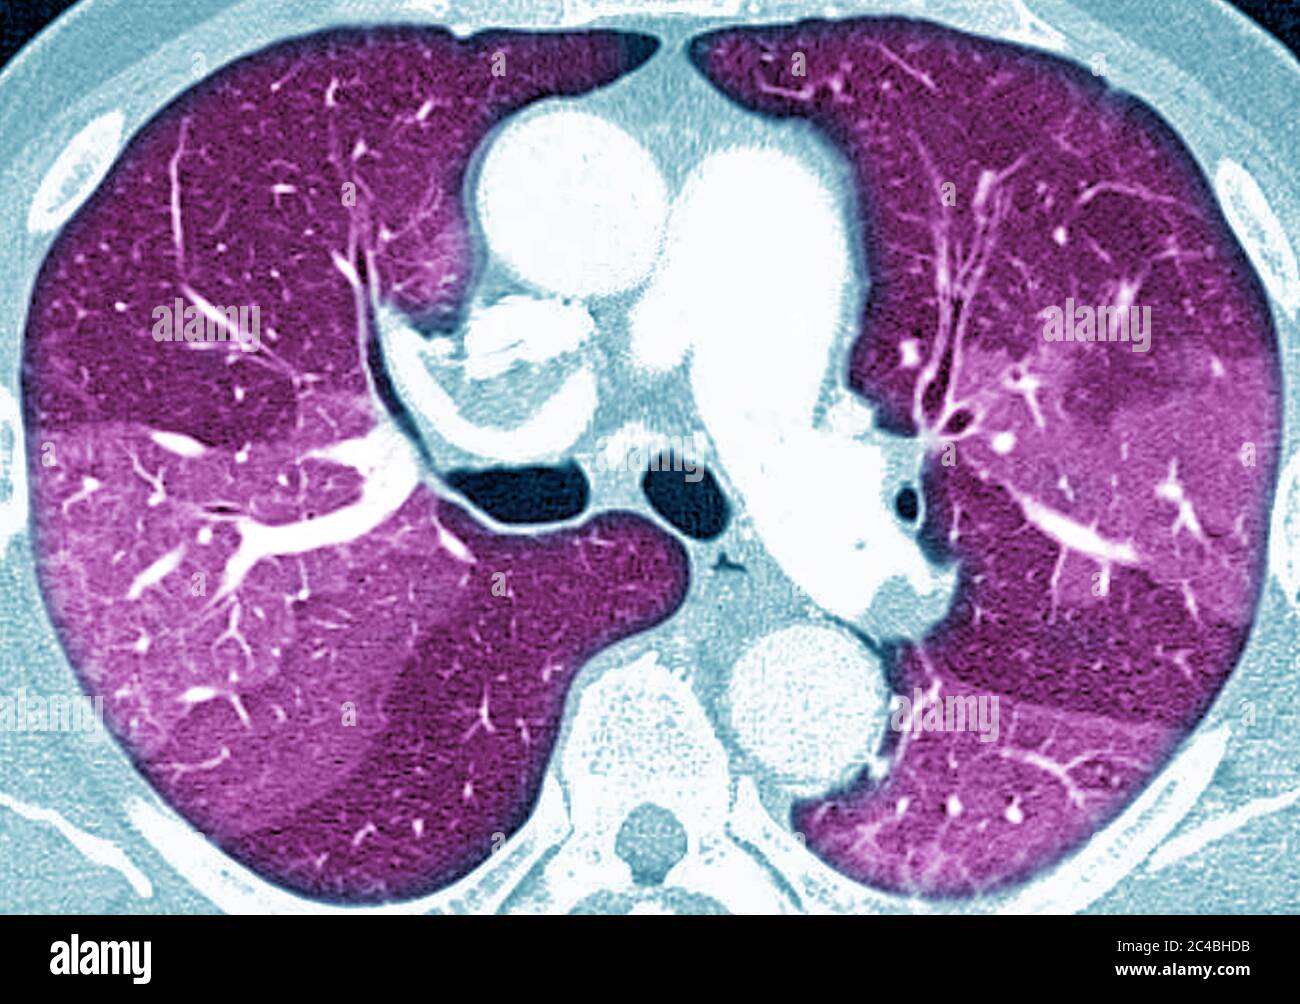

A quoi ressemblent les poumons d’un malade du Covid19 Trou D'air Dans Les Poumons Le pneumothorax est une pénétration d’air dans la cavité pleurale. Il peut être localisé à une partie du poumon ou s'étendre à l'ensemble de l'appareil pulmonaire. Le pneumothorax correspond au remplissage d'air ou de gaz spontané dans la cavité pleurale, constituée par la plèvre, cette. Certains poumons développent de grandes poches d’air (bulles), qui peuvent éclater, entraînant. Ils peuvent aussi. Trou D'air Dans Les Poumons.